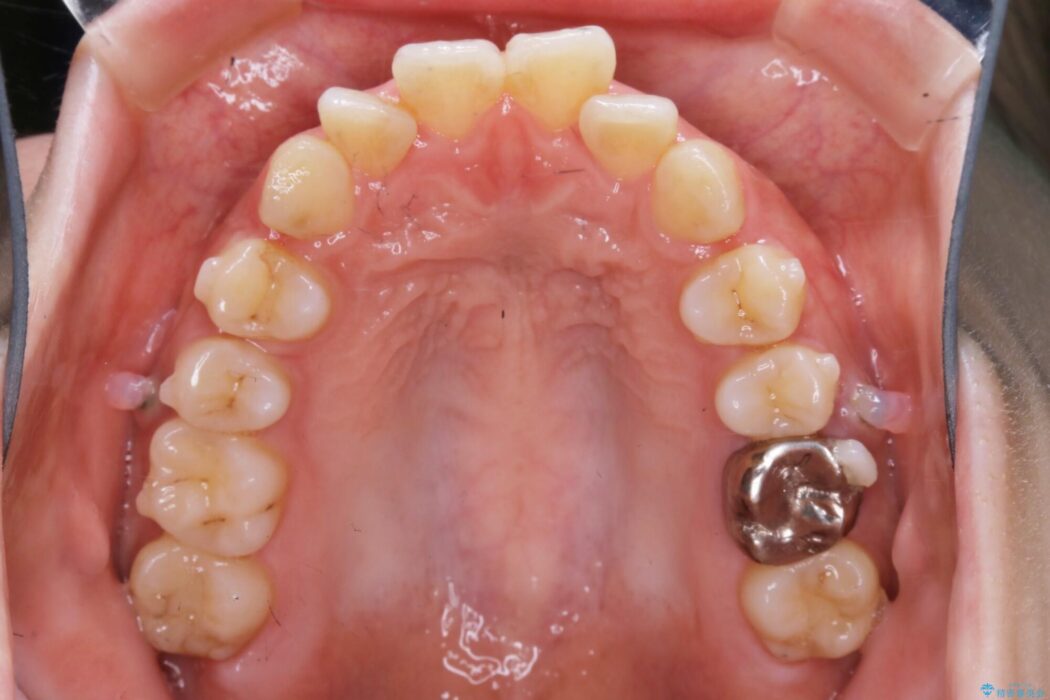

口ゴボに加えて歯列のガタガタを改善したいと来院されました。

患者様のご希望によりインビザライン装置での治療を行いました。

インビザラインは歯を後ろへ動かす動き、非抜歯での矯正治療が得意なため、ワイヤー装置では難しいケースでも対応できる場合があります。

矯正治療において歯並びを整えるためにはスペースが必要になります。

抜歯・歯列幅の拡大・IPR(歯と歯の間を少し削って小さくする)・歯の後方移動などでそのスペースを確保します。

程度にもよりますが口元を下げる治療というと抜歯治療を思い浮かべると思いますが、インビザラインは抜歯をせずとも他の3種類の方法を効率よく活用し治療ができます。